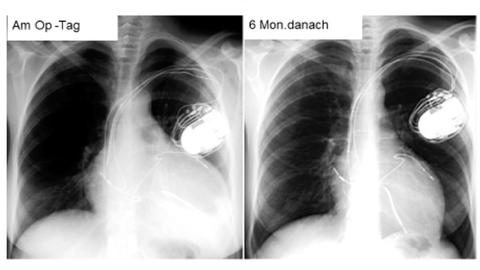

Für die kardiale Resynchronisationstherapie setzt die Ärztin oder der Arzt der Patientin oder dem Patienten in einer Operation meist drei Elektroden ein: Je eine Sonde wird im rechten Vorhof, der rechten Herzkammer sowie der linken Kammer des Herzens platziert. Die Sonden werden an ein Schrittmachergerät angeschlossen, das meist unterhalb des Schlüsselbeins unter der Haut oder dem Brustmuskel implantiert wird. Die Operation dauert etwa 60 bis 90 Minuten. Das Gerät stimuliert beide Herzkammern (biventrikuläre Stimulation) und bewirkt damit, dass diese wieder synchron schlagen. Die Pumpkraft des Herzens nimmt wieder zu. Bei den meisten Patientinnen und Patienten verbessert sich das Befinden durch die Resynchronisationstherapie spürbar. Viele können wieder ohne Atemnot Treppen steigen oder leichte körperliche Arbeit verrichten. Der Erfolg entspricht in etwa der Verbesserung um ein NYHA-Stadium.

Was vor 15 Jahren undenkbar war, ist für Jens Ehrlich heute wie selbstverständlich: ausgedehnte Spaziergänge mit seinem Hund. 2005 führt eine Herzmuskelentzündung (Myokarditis) als Folge einer schweren Erkältung, die der Fotograf wegen beruflichem Stress nicht richtig auskuriert, zu den krankheitstypischen Herzschwäche-Symptomen: Flüssigkeitseinlagerungen im Körper, Leistungsabnahme, Atemnot. Wie der Patient im Zuge der Schrittmachertherapie wieder zu Kräften gefunden hat, was ein Herzschrittmacher für den Alltag bedeutet und wie man mit dem ständigen „Lebensretter“ in der Brust ein aktives Leben führen kann, davon berichtet Ehrlich aus eigenen Erfahrungen